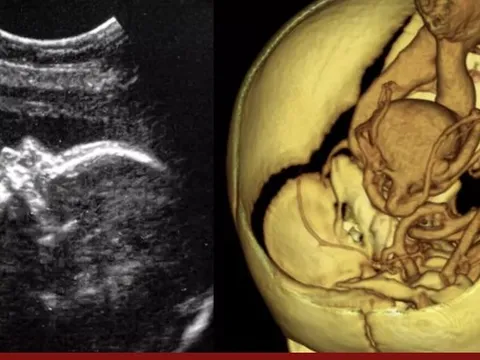

Ca phẫu thuật não đầu tiên trên thai nhi trong bụng mẹ được thực hiện

Các bác sĩ lần đầu tiên thực hiện ca phẫu thuật não của một bào thai trong bụng mẹ để chữa mạch máu bị dị dạng.